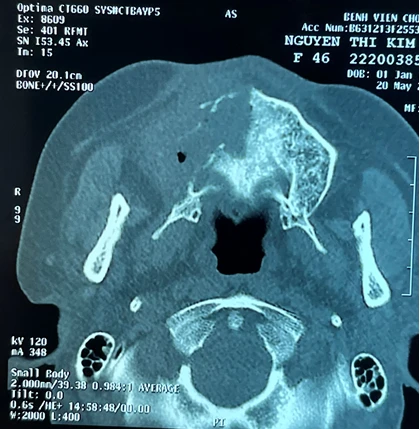

Kết quả chẩn đoán hình ảnh một bệnh nhân bị hoại tử xương hàm mặt và từng mắc COVID-19. Ảnh: BVCC |

Kết quả chụp CT và MRI cho thấy các bệnh nhân có tổn thương, viêm hoại tử lan rộng xoang sọ hàm mặt. Các bác sĩ đã hội chẩn đa chuyên khoa để tiến hành điều trị và can thiệp cho 3 bệnh nhân nữ. Cả 3 bệnh nhân đều không có tiền sử về bệnh tai mũi họng hay răng hàm mặt, có nguy cơ sẽ tử vong nếu không phẫu thuật.

Kết quả phân tích các ca bị hủy hoại xương vùng hàm mặt và xương sọ có sự hiện diện của các loại nấm và vi khuẩn. Các bệnh nhân có biểu hiện chung là đau trong giai đoạn bị nhiễm COVID-19 ở vùng đầu, mặt, răng và tiến triển kéo dài âm ỉ, không giảm giống với bệnh viêm xoang.

Bên cạnh đó, bệnh nhân có thêm các dấu hiệu như sưng viêm mí mắt, viêm sưng vùng sọ trán, hoại tử xương hàm, răng, xương khẩu cái nên khó nhai, hoại tử nặng các mô mềm, hốc mũi lan lên nền sọ.